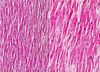

Hydropic degeneration

( edema )

definition , cause , organs

Acute reversible cell injury

caused by various pathogens : ( anoxia , toxins, viruses )

Its the *FIRST *manifistation of all lessions that appear in almost all cell types of aggression , of LOW intensity

Ex. Hydropic degeneration of LIVER

Hydropic degeneration

pathogenesis

- alteration of Na-K pump at the level of cell membrane

- cells can no longer maintain hydro-ionic balance

- sodium ( Na ) and water ENTER the cell

- Potassium ( K ) EXITS the cell